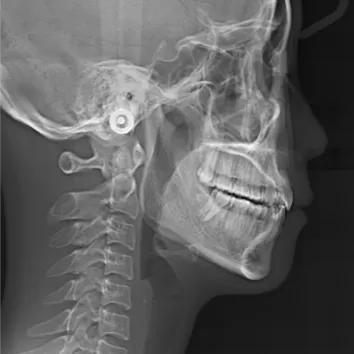

Rayons X avant le traitement

[Radiographie panoramique/Céphalogramme latéral]